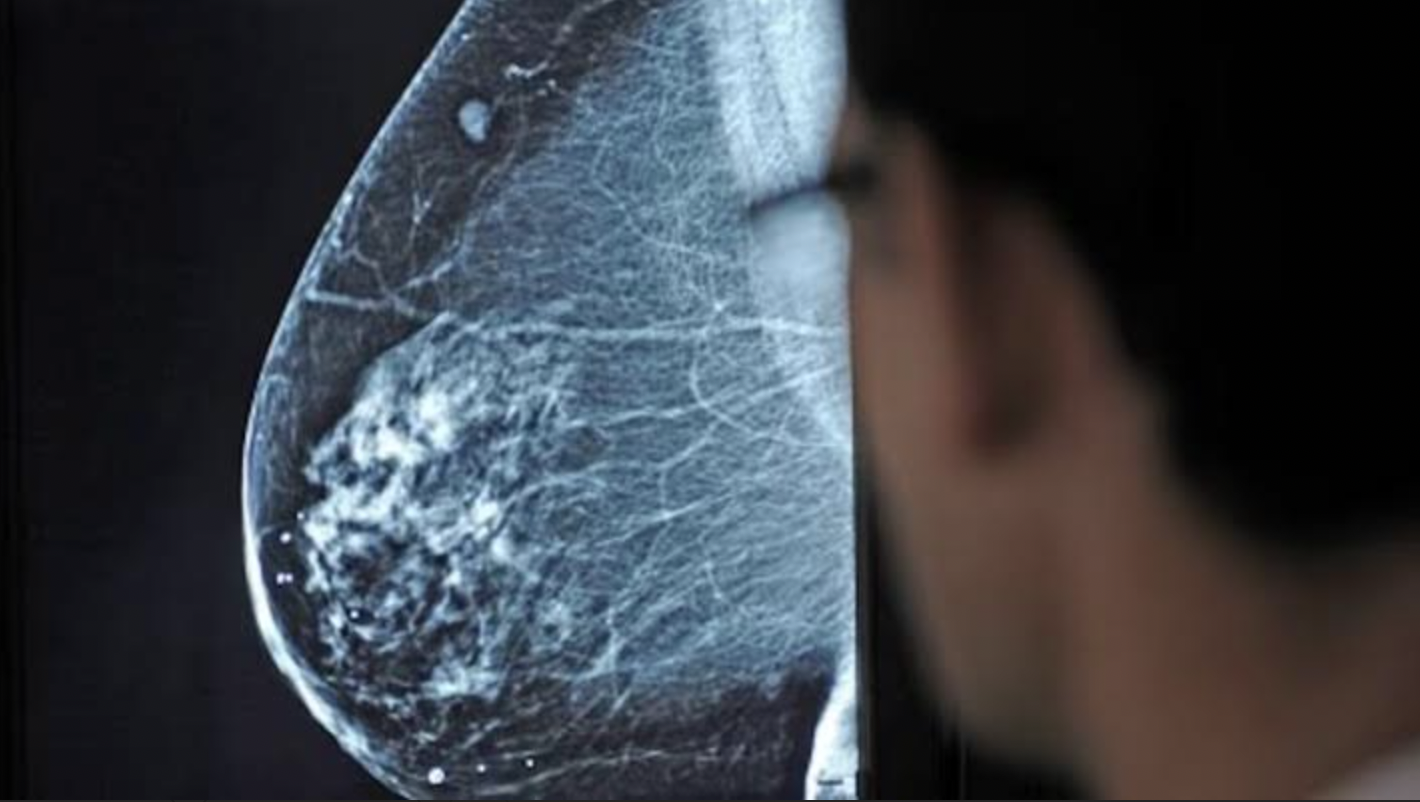

En México, el cáncer de mama sigue siendo una de las principales causas de muerte en mujeres. Con una tasa de 19.8 defunciones por cada 100 mil mujeres y un promedio de 22 fallecimientos diarios, el panorama exige algo más que campañas de concientización: requiere innovación clínica con impacto real.

En este contexto, ALIA Health, spin-off de TecSalud del Tecnológico de Monterrey, y ÜMA Tech IA, Partner de Servicios de Google Cloud para el sector salud en Latinoamérica, anunciaron el desarrollo de ALIA Health Risk Platform, una plataforma basada en inteligencia artificial que permite anticipar el riesgo de desarrollar cáncer de mama en un horizonte de cinco años, a partir de mamografías convencionales.

El corazón de la plataforma es Mammorisk+, un modelo predictivo entrenado con datos reales de práctica clínica. A diferencia de herramientas que detectan lesiones ya sospechosas, este modelo estima la probabilidad futura de desarrollar cáncer de mama en mujeres cuyas mamografías no muestran hallazgos preocupantes.

El objetivo es claro: actuar antes del diagnóstico, en la etapa donde se definen estrategias de prevención, seguimiento y personalización del tamizaje.

En un país donde solo el 27% de las mujeres en edad de riesgo tuvo acceso a una mastografía el último año y donde el 64% de los casos se detectan en etapas II o III —cuando los tratamientos son más costosos y la supervivencia disminuye—, esta herramienta podría representar un punto de inflexión.